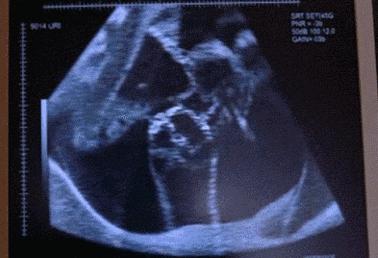

看看调皮的宝宝到底在肚子里有多闹腾?

1.绕着麻麻的肚子游一圈~我爱游泳!

2. 胎儿平衡力考试:及格!

3. 抖抖手啊,跺跺脚啊~~

4. 龟~派~气~功!

5. 麻麻,你肚皮上有条线很挡光哦!

6. 看我能把麻麻的肚皮撑多大!

7. 小样,我知道你在看着我呢。

8. 爸比,我在这里,看这里

9. 大白天麻麻怎么又睡觉了,起来做个运动吧!